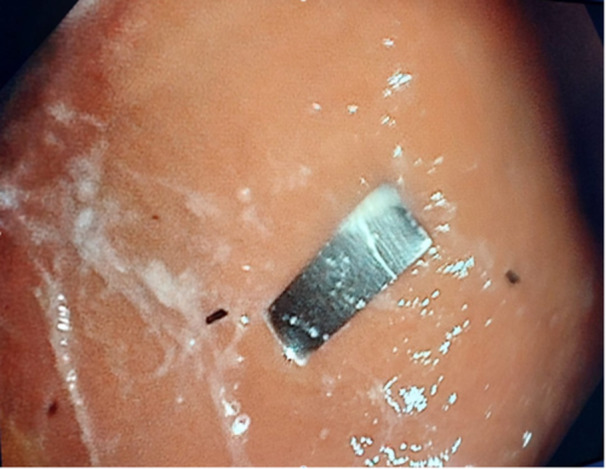

烟草过滤嘴中的金属板:儿科的新挑战。

Metallic plate in tobacco filters: A new pediatric challenge.